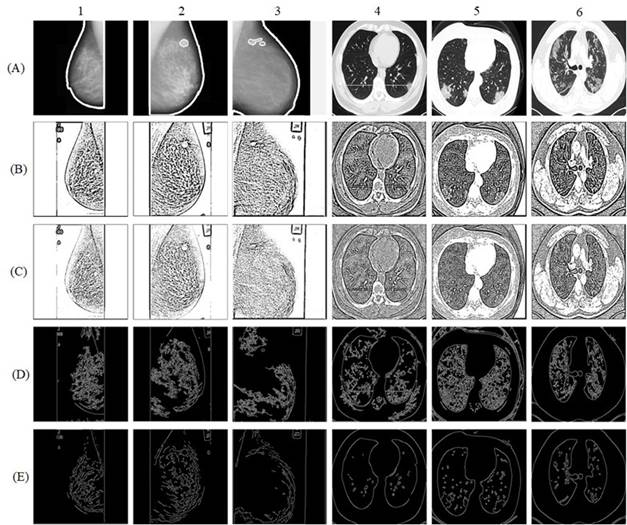

Finally, Figure 5 presents a comparison at the image quality and detection level between the proposed method and other thresholding techniques, such as mean thresholding and Gaussian thresholding, as well as the Canny algorithm and the HED algorithm for mammography and CT images and are shown respectively from top to bottom.

The images obtained by applying the mean and Gaussian thresholding techniques generate effects in the image in sections of no interest and demarcate almost the entire image as a region of interest. Under the same behavior, applying the Canny algorithm also generated sections of no interest as if they were regions of interest, and in the case of the mammograms, the identification of the external border was not completed, while in the CT scans the external borders were identified, but redundancy was generated in the internal contours. In addition, the HED algorithm-generated redundancy in the internal contours in mammograms, while in CT scans it improved its performance in terms of external contours. In general, the proposed method improved image features, identified regions of interest and mitigated redundancy effects in both mammograms and CT scans.